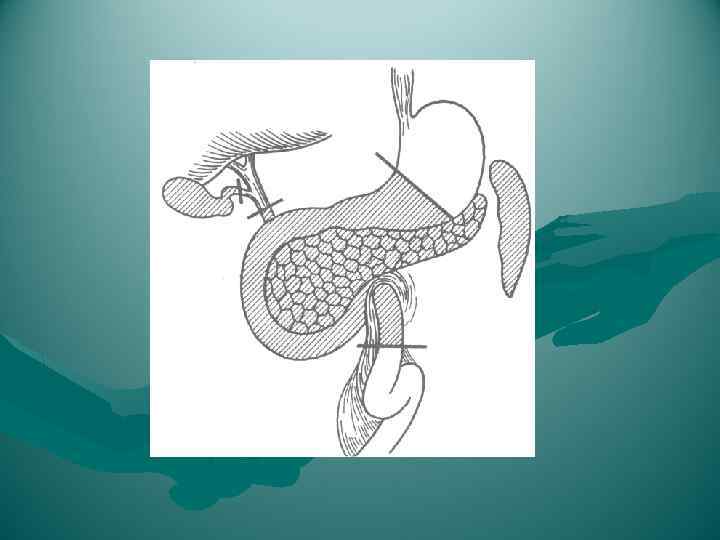

Взаимоотношение поджелудочной железы с двенадцатиперстной кишкой, общим желчным протоком, воротной и нижней полой венами, брюшной аортой и ее ветвями. 1 — v. cava inferior; 2 — aorta abdominalis; 3 — truncus coeliacus; 4 — a. gastrica sinistra; 5 — a. lienalis; 6 — v. lienalis; 7 — v. mesenterica inferior; 8 — a. mesenterica superior; 9 — v. mesenterica superior; 10 — caput pancreatis; 11 — duodenum; 12 — a. gastroduodenalis; 13 — a. hepatica communis; 14 — a. hepatica propria; 15 — ductus choledochus; 16 — a. gastrica dextra; 17 — v. portae; 18 — ductus cysticus; 19 — ductus hepaticus communis.

Взаимоотношение поджелудочной железы с двенадцатиперстной кишкой, общим желчным протоком, воротной и нижней полой венами, брюшной аортой и ее ветвями. 1 — v. cava inferior; 2 — aorta abdominalis; 3 — truncus coeliacus; 4 — a. gastrica sinistra; 5 — a. lienalis; 6 — v. lienalis; 7 — v. mesenterica inferior; 8 — a. mesenterica superior; 9 — v. mesenterica superior; 10 — caput pancreatis; 11 — duodenum; 12 — a. gastroduodenalis; 13 — a. hepatica communis; 14 — a. hepatica propria; 15 — ductus choledochus; 16 — a. gastrica dextra; 17 — v. portae; 18 — ductus cysticus; 19 — ductus hepaticus communis.